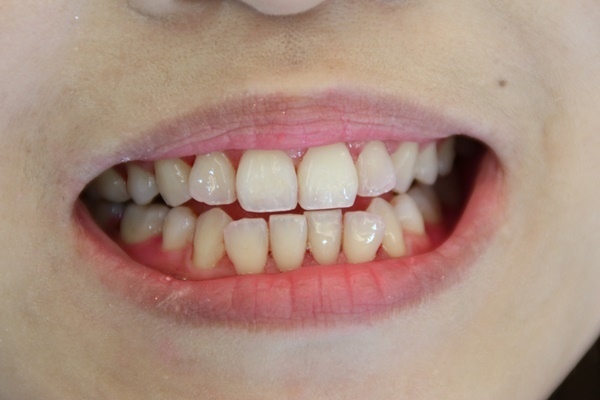

這是洗牙前的牙齒照,還好我再來前有先刷個牙,不然拍起來就搞笑了!

醫生會在這之前檢查你的牙齒有沒有牙菌斑,會幫你塗上檢驗牙菌斑的藥劑,這樣才可以更清楚知道你哪邊需要特別牙菌斑處理~!

開始洗牙了唷~!你看看我像不像吸血鬼~!我的牙菌斑是超級多的呢~!醫生說我算是蠻特殊的體質,難得看到這麼多的~!!哈哈~!不過最開心的是,我可都沒有蛀牙呢~!!

洗牙的過程就是會一直反覆的漱口,又洗~!就是要把你口腔裡的所有牙結石跟你說掰掰~!陳醫師是個超細心的醫師,洗牙都不會痛!!

在醫生的巧手下,我的牙齒洗乾淨了耶~!醫生還幫我的牙齒稍微了小小美白一下!!

挖賽~!我的牙齒變得超級無敵乾淨的!!有被我的牙齒閃到嗎?